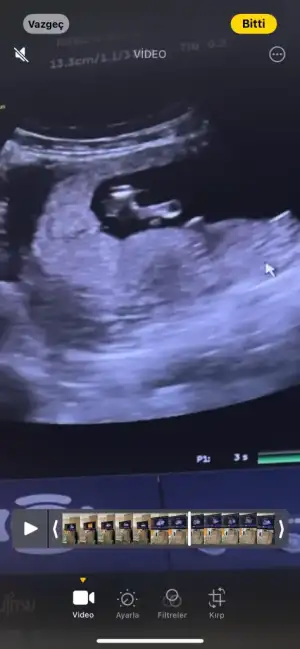

Kızlar bugün dayanamayıp başka bir doktora gittim, dr bacak arasını gösterdi. Videoya çekmiştik, bu görüntüleri videodan çektim. Erkek dedi, erkek bebek bekleyenler sizin de böyle mi acaba?🙈

Renkli kan akımına baktı mı? Kordon falan değilse erkeğe benzettim ben de.